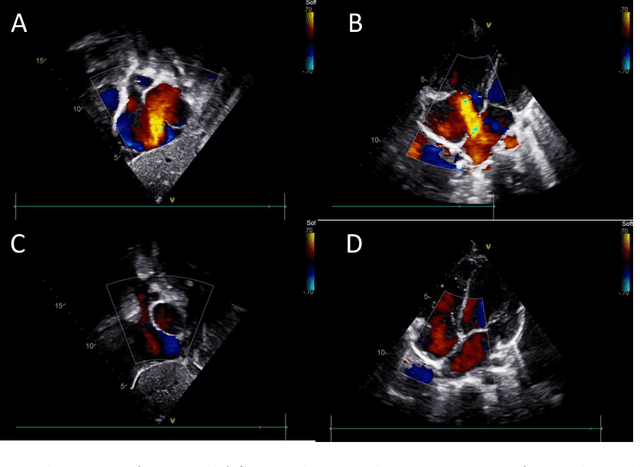

Abstract:Segmenting internal structure from echocardiography is essential for the diagnosis and treatment of various heart diseases. Semi-supervised learning shows its ability in alleviating annotations scarcity. While existing semi-supervised methods have been successful in image segmentation across various medical imaging modalities, few have attempted to design methods specifically addressing the challenges posed by the poor contrast, blurred edge details and noise of echocardiography. These characteristics pose challenges to the generation of high-quality pseudo-labels in semi-supervised segmentation based on Mean Teacher. Inspired by human reflection on erroneous practices, we devise an error reflection strategy for echocardiography semi-supervised segmentation architecture. The process triggers the model to reflect on inaccuracies in unlabeled image segmentation, thereby enhancing the robustness of pseudo-label generation. Specifically, the strategy is divided into two steps. The first step is called reconstruction reflection. The network is tasked with reconstructing authentic proxy images from the semantic masks of unlabeled images and their auxiliary sketches, while maximizing the structural similarity between the original inputs and the proxies. The second step is called guidance correction. Reconstruction error maps decouple unreliable segmentation regions. Then, reliable data that are more likely to occur near high-density areas are leveraged to guide the optimization of unreliable data potentially located around decision boundaries. Additionally, we introduce an effective data augmentation strategy, termed as multi-scale mixing up strategy, to minimize the empirical distribution gap between labeled and unlabeled images and perceive diverse scales of cardiac anatomical structures. Extensive experiments demonstrate the competitiveness of the proposed method.

Abstract:Purpose: Congenital heart defect (CHD) is the most common birth defect. Thoracic echocardiography (TTE) can provide sufficient cardiac structure information, evaluate hemodynamics and cardiac function, and is an effective method for atrial septal defect (ASD) examination. This paper aims to study a deep learning method based on cardiac ultrasound video to assist in ASD diagnosis. Materials and methods: We select two standard views of the atrial septum (subAS) and low parasternal four-compartment view (LPS4C) as the two views to identify ASD. We enlist data from 300 children patients as part of a double-blind experiment for five-fold cross-validation to verify the performance of our model. In addition, data from 30 children patients (15 positives and 15 negatives) are collected for clinician testing and compared to our model test results (these 30 samples do not participate in model training). We propose an echocardiography video-based atrial septal defect diagnosis system. In our model, we present a block random selection, maximal agreement decision and frame sampling strategy for training and testing respectively, resNet18 and r3D networks are used to extract the frame features and aggregate them to build a rich video-level representation. Results: We validate our model using our private dataset by five-cross validation. For ASD detection, we achieve 89.33 AUC, 84.95 accuracy, 85.70 sensitivity, 81.51 specificity and 81.99 F1 score. Conclusion: The proposed model is multiple instances learning-based deep learning model for video atrial septal defect detection which effectively improves ASD detection accuracy when compared to the performances of previous networks and clinical doctors.